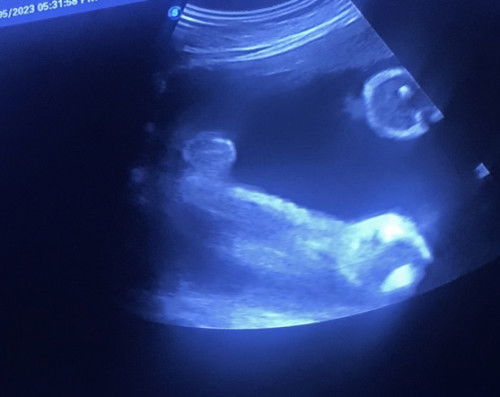

Girl or boy?

Hi ibu ibu. boleh tak siapa teka ni girl ke boy?

View ni x berapa jelas lg sis.. nk girl takut tu tali pusat dia pulak.. nk kata boy pun xleh jgk sbb baby x berapa nk kangkang sgt ni 😅

Tk pasti sis, sbb ad je boy yg kepit bkn spnjang mse dia nk tnjuk pistol. Cuba scan bulan dpn dri angle lain pulak.

Girl nampak mcm bege , kalau boy pistol

girl.. burger sign

boy kompom